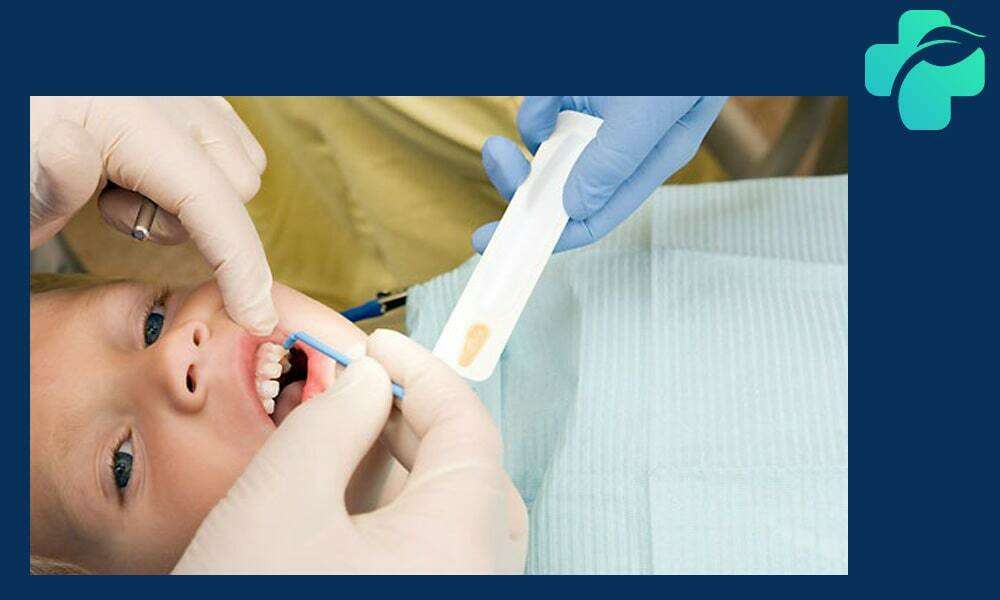

فلوراید تراپی در کودکان

کودکان به دلیل تازه بودن دندان های شیری و رشد دندان های دائمی در معرض خطر بیشتری برای پوسیدگی دندان هستند. به همین خاطر، فلوراید درمانی در کودکان از اهمیت ویژه ای برخوردار است.

فلوراید تراپی در کودکان به روش های مختلفی مانند خمیر فلوراید، وارنیش فلوراید و ژل فلوراید انجام می شود. وارنیش فلوراید نوعی پوشش محافظ است که به سادگی روی دندان ها مالیده شده و به مدت طولانی در تماس با مینای دندان باقی می ماند. این پوشش باعث سختی بیشتر مینای دندان و کاهش پوسیدگی می شود.

برای محافظت بهتر از دندان های کودکان توصیه می شود که این درمان به طور منظم، حداقل هر شش ماه یکبار در دندانپزشکی اطفال انجام شود. همچنین والدین با آموزش روش های صحیح مسواک زدن و رعایت بهداشت دهان می توانند اثربخشی فلوراید درمانی را افزایش دهند.